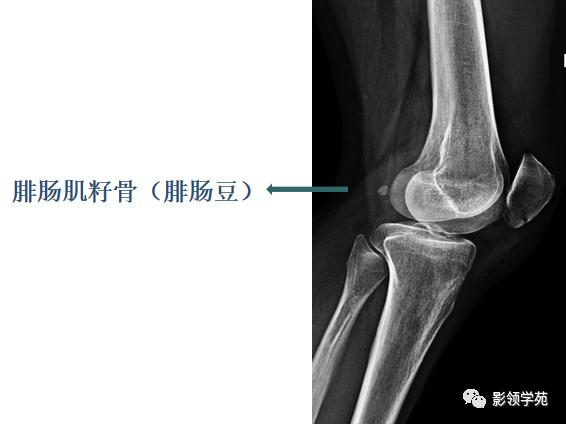

籽骨

籽骨是由肌腱骨化而成,有改变压力消除肌腱与骨面之间的摩擦、变换肌的牵引力方向加大肌及稳定关节的作用。